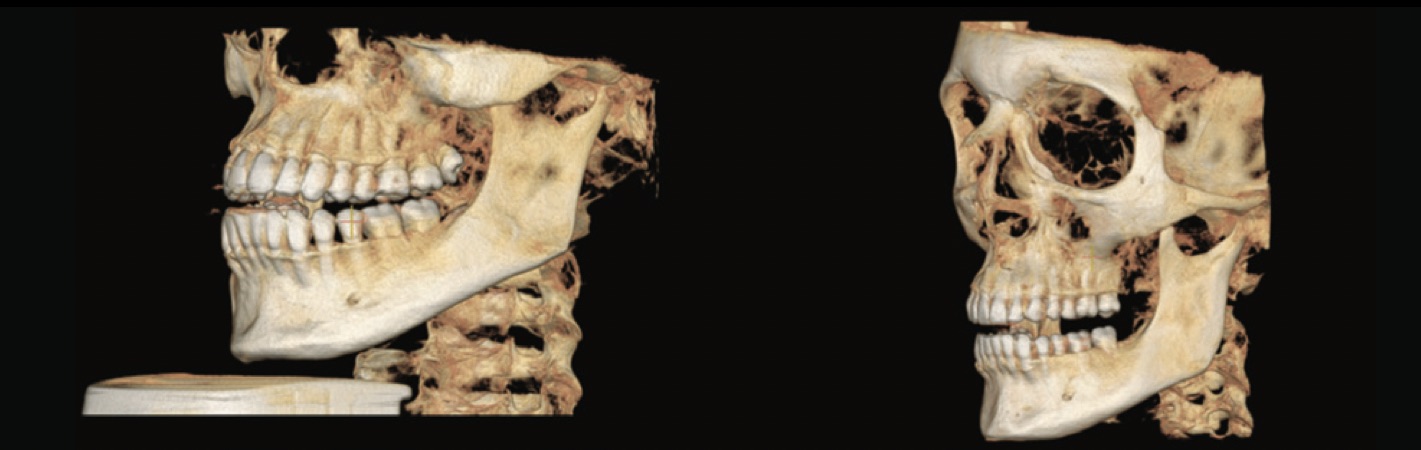

Comparaison d'images CBCT FOV 16 x 10 versus FOV 15 x 15.

Analyse céphalométrique 3D : Oubliez les limites de la radiologie 2D telles que les erreurs de positionnement du patient, le grossissement des structures bilatérales et le chevauchement d'autres structures craniofaciales et obtenez une image 3D des structures vitales avec une meilleure localisation des repères anatomiques dans l'analyse céphalométrique.